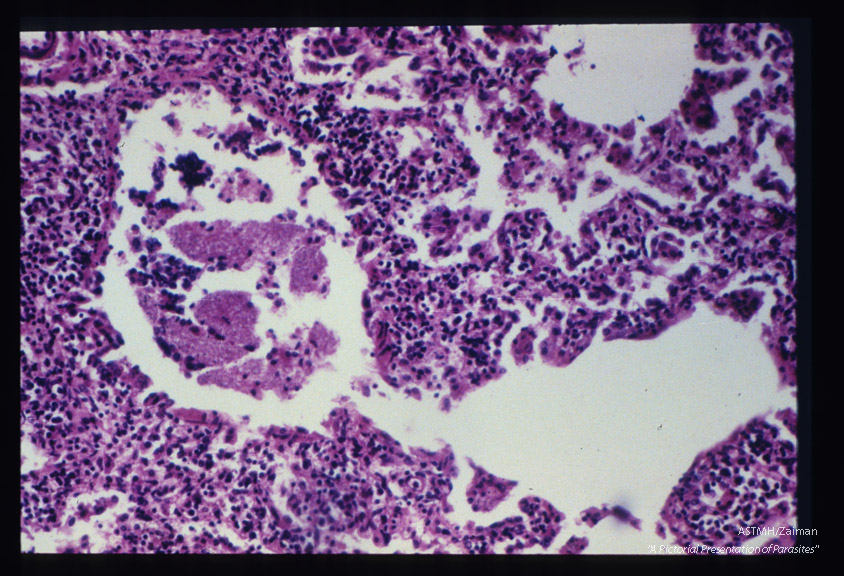

Pneumonia. The alveolar spaces contain honeycomb material. A lining of pinkish red material defines the alveolar space. Note the thickened alveolar walls which are intensively invaded by plasma cells and lymphocytes.

Pneumocystis carinii

Description: Pneumonia. The alveolar spaces contain honeycomb material. A lining of pinkish red material defines the alveolar space. Note the thickened alveolar walls which are intensively invaded by plasma cells and lymphocytes.